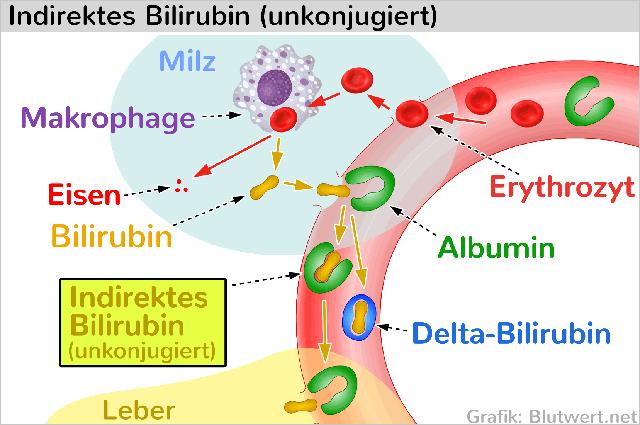

2. Unterscheidung der Bilirubinfraktionen

Bei der Bestimmung des Bilirubinwertes werden verschiedene Fraktionen unterschieden. Das indirekte Bilirubin ist die unkonjugierte, wasserunlösliche Form, die an das Protein Albumin gebunden ist. Das direkte Bilirubin hingegen ist die konjugierte, wasserlösliche Form. Zusätzlich gibt es noch das Delta-Bilirubin, welches eine kovalente Bindung mit Albumin eingeht.

Des Weiteren kann eine Gelbsucht durch einen verstärkten Abbau von roten Blutkörperchen (Hämolyse) verursacht werden. Dies kann beispielsweise bei Stoffwechselerkrankungen, als Nebenwirkung von Medikamenten oder bei großen Blutergüssen auftreten.

Erhöhte Bilirubinspiegel können verschiedene Ursachen haben. Eine Störung des Bilirubinstoffwechsels kann beispielsweise zu einer Hyperbilirubinämie führen. Bei der erblichen Krankheit Morbus Meulengracht ist die Aufnahme des unkonjugierten Bilirubins in die Leberzellen gestört, während beim Criggler-Najjar-Syndrom die Glucuronidierung zu gering ist. In beiden Fällen ist der Anteil des indirekten Bilirubins erhöht.

Des Weiteren kann eine Hyperbilirubinämie auf Beeinträchtigungen der Leberfunktion zurückgehen, wie beispielsweise bei einer Hepatitis, Leberzirrhose, Fettleber oder Cholestase (Gallenstauung). Auch ein verstärkter Abbau von Erythrozyten (Hämolyse) kann zu erhöhten Bilirubinspiegeln und damit zu einer Gelbsucht führen.